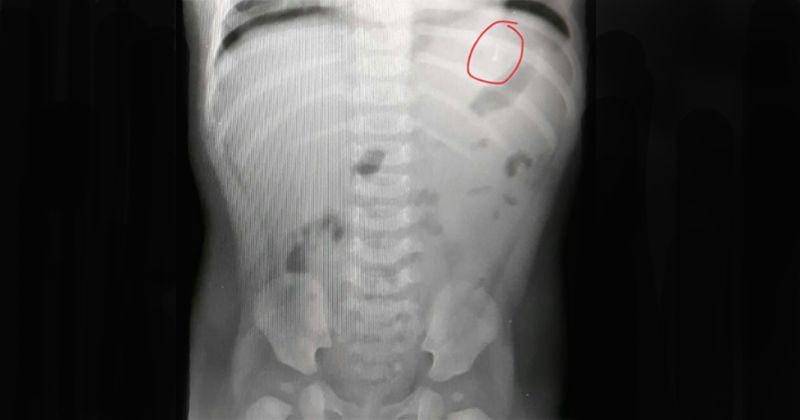

Seorang bayi berusia 9 bulan dibawa oleh orangtuanya untuk menemui dokter. Bayi ini merupakan salah satu pasien dari dr. Kanya Fidzuno Sp.A.

Orangtua melaporkan kalau ia menduga anaknya menelan cincin karena secara sadar orangtua tersebut telah memakaikan cincin ke bayinya dengan ukuran yang agak kebesaran agar cincin tersebut bisa dipakai lebih lama. Setelah sadar cincin tidak ada di jari bayinya dan anaknya diare, maka orangtua tersebut memutuskan untuk memeriksakan bayinya ke dokter.

Menurut penjelasan dr. Kanya, banyak sekali kejadian serupa di mana bayi menelan benda asing ke dalam tubuhnya kemudian terjadi reaksi pada tubuh Si Anak. Ini tidak bisa dianggap sepele. Benda asing bisa masuk ke saluran pencernaan, atau bahkan ke organ lainnya.